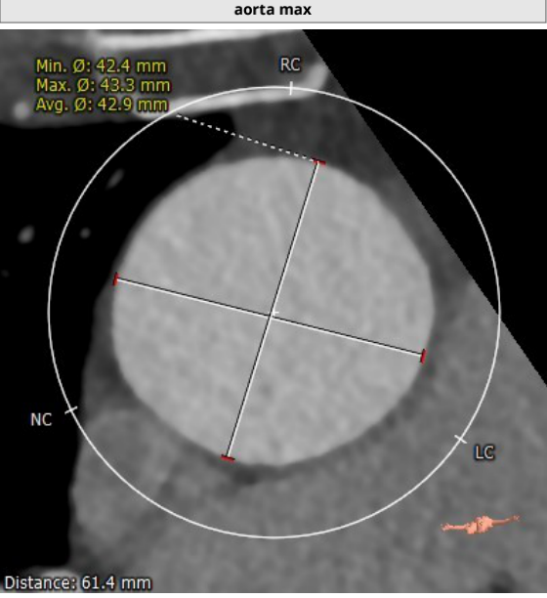

患者主动脉根部、冠状动脉、主动脉增强CT扫描,通过专业评估软件分析提示该患者主动脉瓣为功能型二叶瓣、中度钙化,左右冠窦可见融合、瓦氏窦结构较大,左右冠开口高度尚可,升主动脉最宽处约42.9mm,左室明显扩大。主动脉瓣环平均径约26.3mm,流出道平均径约27.5mm,STJ平均径约34.3mm,双侧股动脉直径均大于6mm。冠脉见钙化灶,钙化积分总和为1590.2;冠脉CTA提示:“左主干、三支冠状动脉粥样硬化改变,局部管腔可见40~60%狭窄”。

升主61.4mm处增宽:42.9mm